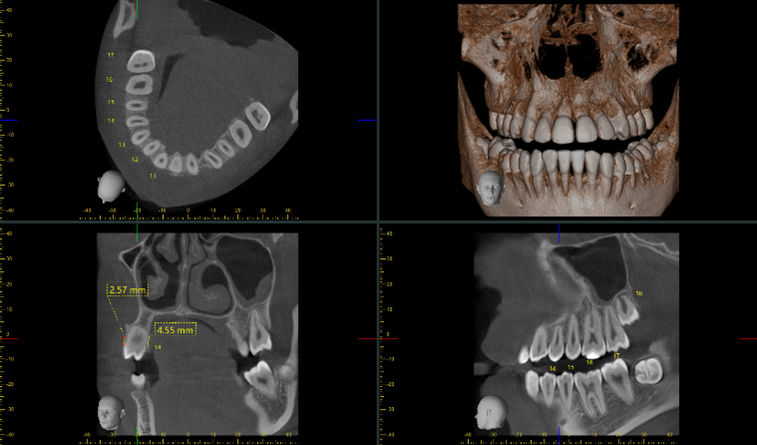

El dentista podrá hacer en el ordenador cortes bi y tridimensionales de las imágenes que obtiene. Le permitirá observar con detalle cualquier característica de la boca del paciente como:

- La densidad y calidad del hueso.

- Por donde pasan los vasos sanguíneos y nervios.

- El TAC dental asegura una buena precisión para diseñar el plan de tratamiento odontológico más adecuado.

Con esta prueba diagnóstica, es posible realizar la técnica implantológica de carga inmediata, se trata de un procedimiento que permite colocarle al paciente en una misma cita la corona y el implante.